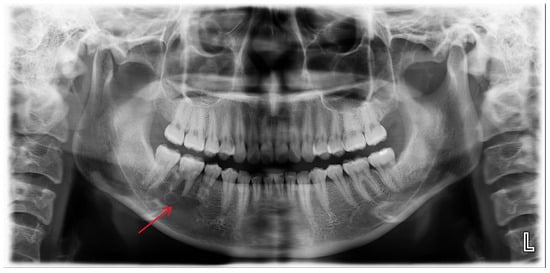

A 25-year-old female was referred to the Department of Oral and Maxillofacial Surgery from a local dental clinic with a primary concern of an intraosseous lesion located below the root apex of the right mandibular first molar. The patient did not report any clinical symptoms. Panorama revealed a multilocular radiolucent lesion with relatively well-defined borders and sclerotic margins in the region of the right mandibular molar. In addition, root resorption was observed in the right mandibular second premolar and first molar (Figure 1). Cone-beam computed tomography (CBCT) revealed thinning of the lingual cortical bone in the areas surrounding the right mandibular second premolar and first molar, as well as inferior displacement of the right mandibular canal (Figure 2). Both the right mandibular second premolar and first molar exhibited slight mobility and percussion sensitivity, while electric pulp testing was positive. Incisional biopsy was the ameloblastoma. To treat the lesion and minimize the risk of recurrence, resection and reconstruction were planned, and virtual surgical planning was performed in collaboration with the SEEANN solution (SEEANN solution, Seoul, Korea). To ensure accurate translation of the VSP to the actual surgery, template models were fabricated for preoperative simulation and intraoperative reference, and surgical guides were designed with multiple registration points for optimal positioning verification during the procedure.

Figure 1.

A multilocular radiolucent lesion with relatively well-defined borders and sclerotic margins in the right mandibular molar region, along with root resorption of the right mandibular second premolar and first molar (red arrow).